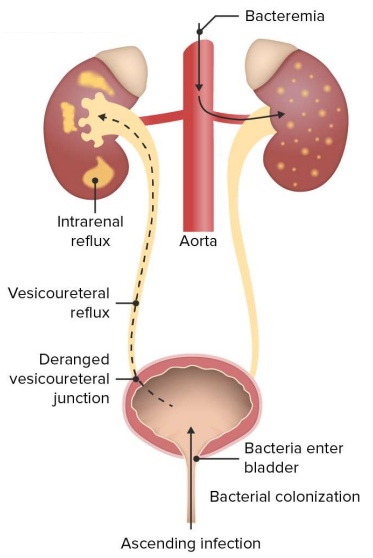

- 외부 환경에서 bacteria가 urethra(요도)로 들어가, 신체의 면역 방어 체계를 깨뜨리고 uniray tract(비뇨기계)에 감염을 유발한 상태.

(Conditions that happen when bacteria from the external environment enter the urethra, evade the body’s immune defenses and cause urinary tract infection)

- Acute pyelonephritis (APN) : 보통 세균이 하부 요로에서 콩팥깔때기(renal pelvis), 콩팥 실질(parenchyma)로 올라가면서 발생. 며칠~몇 주 내로 발병. 가끔 혈행성(hematogenous)으로도 발생함.

- Complicated APN : DM, 종양, 면역저하, 해부학적 문제 등 전신 질환과 함께 나타나는 경우

- Noncomplicated APN